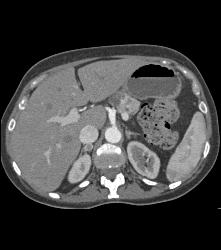

Lower Pole Right Renal Cell Carcinoma With Cystic Pancreatic Lesion in Von Hippel-Lindau syndrome (VHL) - See Sequence